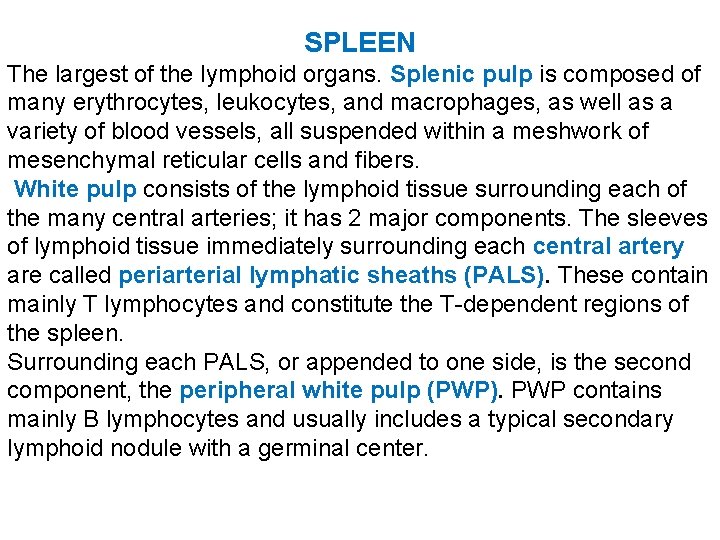

SPLEEN The largest of the lymphoid organs. Splenic pulp is composed of many erythrocytes, leukocytes, and macrophages, as well as a variety of blood vessels, all suspended within a meshwork of mesenchymal reticular cells and fibers. White pulp consists of the lymphoid tissue surrounding each of the many central arteries; it has 2 major components. The sleeves of lymphoid tissue immediately surrounding each central artery are called periarterial lymphatic sheaths (PALS). These contain mainly T lymphocytes and constitute the T-dependent regions of the spleen. Surrounding each PALS, or appended to one side, is the second component, the peripheral white pulp (PWP). PWP contains mainly B lymphocytes and usually includes a typical secondary lymphoid nodule with a germinal center.

Red pulp makes up most of the spleen and also has 2 major components: the red pulp cords and the splenic sinusoids that lie between them. The red pulp (Billroth’s) cords are irregular sheets of reticular connective tissue that branch and anastomose to surround the sinuses. In addition to reticular cells and fibers, the cords contain many cell types, including all the formed elements of blood, dendritic cells, macrophages, plasma cells, and lymphocytes. Splenic sinusoids differ from common capillaries: the lumen is wider and more irregular; there are 2 -3 - m spaces between the lining endothelial cells; and there is a sparse, discontinuous basal lamina that is composed largely of reticular fibers arranged in bands that run roughly perpendicular to the length of the vessel. The marginal zone forms a border between the white and red pulp; it consists of a moatlike arrangement of blood sinuses and loose lymphoid tissue containing few lymphocytes.